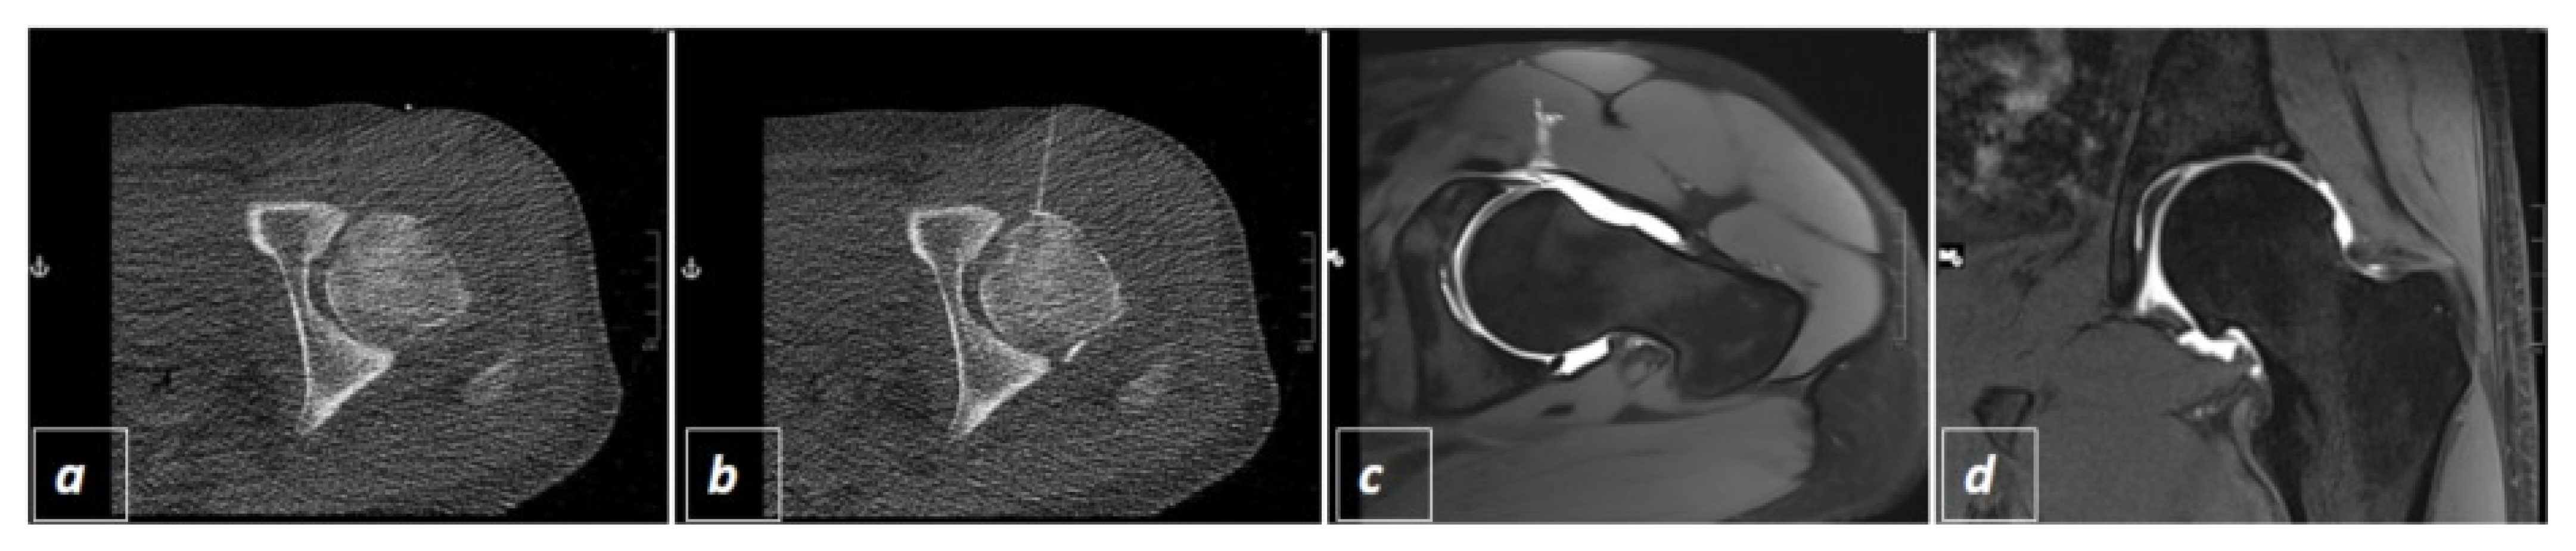

2.2. CT-Guided Joint Injections

2.3. The Three Different Examination Protocols

2.4. Radiation Exposure and Interventional Success